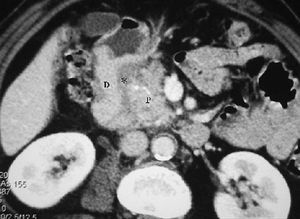

Fig. 9--Diverticulitis duodenal. (A) En la ecografía se observa un divertículo (flechas) con engrosamiento de pared duodenal (D) y alteración de la grasa adyacente (*). (B) Tomografía computarizada de otro paciente con inflamación de divertículo duodenal. Se oberva una lesión quística (punta de flecha) de pared gruesa y borrosa, con material en su interior. P: Páncreas.

Fig. 1--Malrotación intestinal. (A) y (B) Tomografía computarizada con contraste oral e intevenoso mostrando inversión de la arteria mesentérica superior (AMS) (punta de flecha) y la vena mesentérica superior (flecha). La tercera porción duodenal (D) no cruza la línea media entre la aorta y la AMS, localizándose las asas de yeyuno a la derecha.